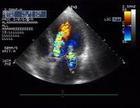

彩色多普勒血流显像

彩色多普勒血流显像(color Doppler flow imaging,CDFI)

彩色多普勒又称二维多普勒,它把所得的血流信息经相位检测、自相关处理、彩色灰阶编码,把平均血流速度资料以彩色显示,并将其组合,叠加显示在B型灰阶图像上。它较直观地显示血流,对血流的性质和流速在心脏、血管内的分布较脉冲多普勒更快、更直观地显示。对左向右分流血流以及瓣口返流血流的显示有独到的优越性。但对血流的定量不如脉冲波和连续波多普勒。

1、血流方向 在频谱多普勒显示中,以零基线区分血流方向。在零基线上方者示血流流向探头,零基线以下者示血流离开探头。在CDI中,以彩色编码表示血流方问,红色或黄色色谱表示血流流向探头(热色);而以蓝色或蓝绿色色谱表示血流流离探头(冷色)。